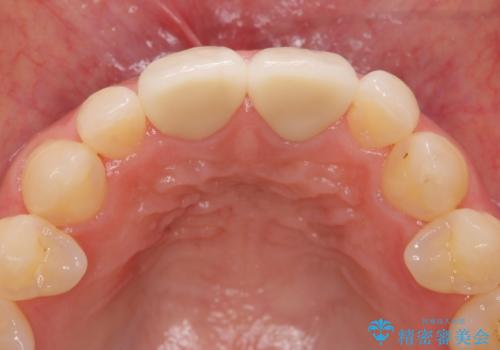

短期集中 前歯審美治療

- 3週間後に迫った結婚式までになんとか前歯をきれいにしたいという希望で来院されました。

一回の治療時間を長く取り、限られた時間で最大限の結果を出せるよう集中治療を計画します。

- 32万円(仮歯・ファイバーコア・ジルコニアクラウンスペシャル×2)費用は治療当時の料金となります

ただ見えるクラウンを白くきれいにするのではなく、長期的な歯の予後を考えると根管治療・ファイバーコア築盛・精密な歯牙形成等クリアすべき条件は多々あると言えます。